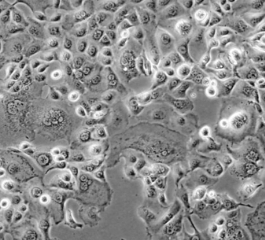

1. 形态特征:上皮细胞样,贴壁生长;细胞表面具有微绒毛结构。